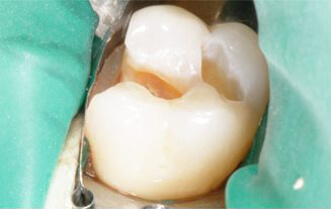

Проблема. Кариозные поражения

Решение. Восстановление кариозных поражений композитными пломбами.